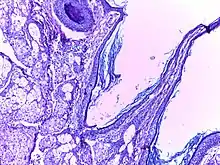

![]() | Foreign body granuloma | Granulomatous reaction to keratin characterized by foreign body giant cells and chronic inflammatory cells. | Category: Histopathology of foreign body granuloma | Foreign body granuloma, silicone granuloma |